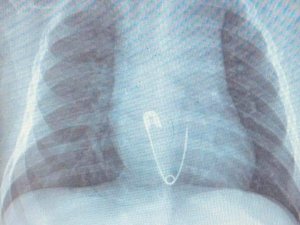

5 aylık bebeğin yuttuğu çengelli iğne operasyonla çıkarıldı